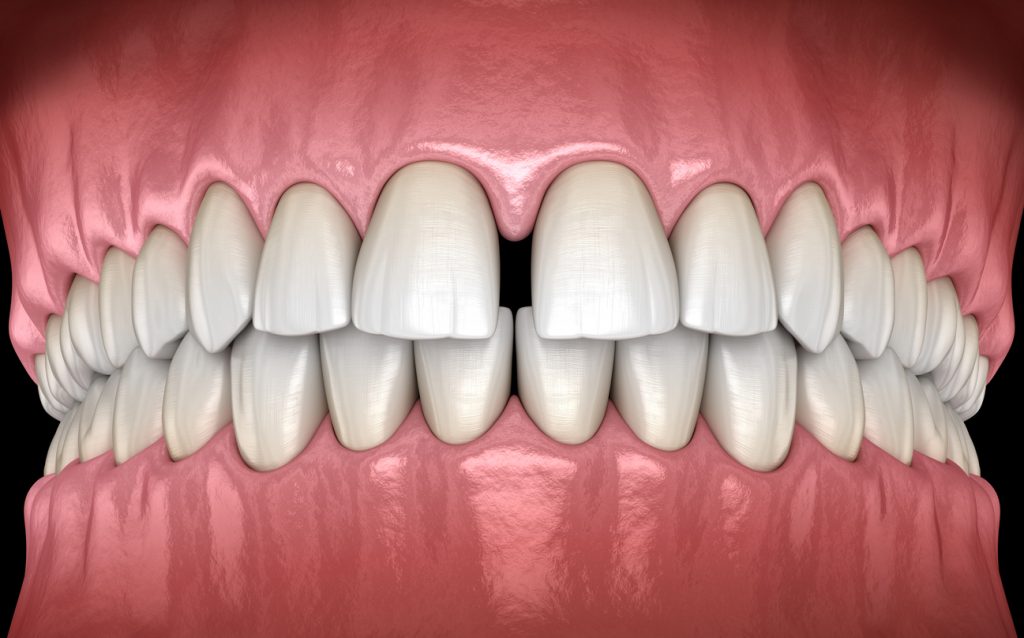

Once considered a treatment for children and teens, the number of adults getting braces and other orthodontic treatments is on the rise. According to the American Association of Orthodontics, in 2014 the number of adults who had seen an orthodontist had risen to 1.4 million, increasing 40% from 2012. From traditional braces to Invisalign, […]